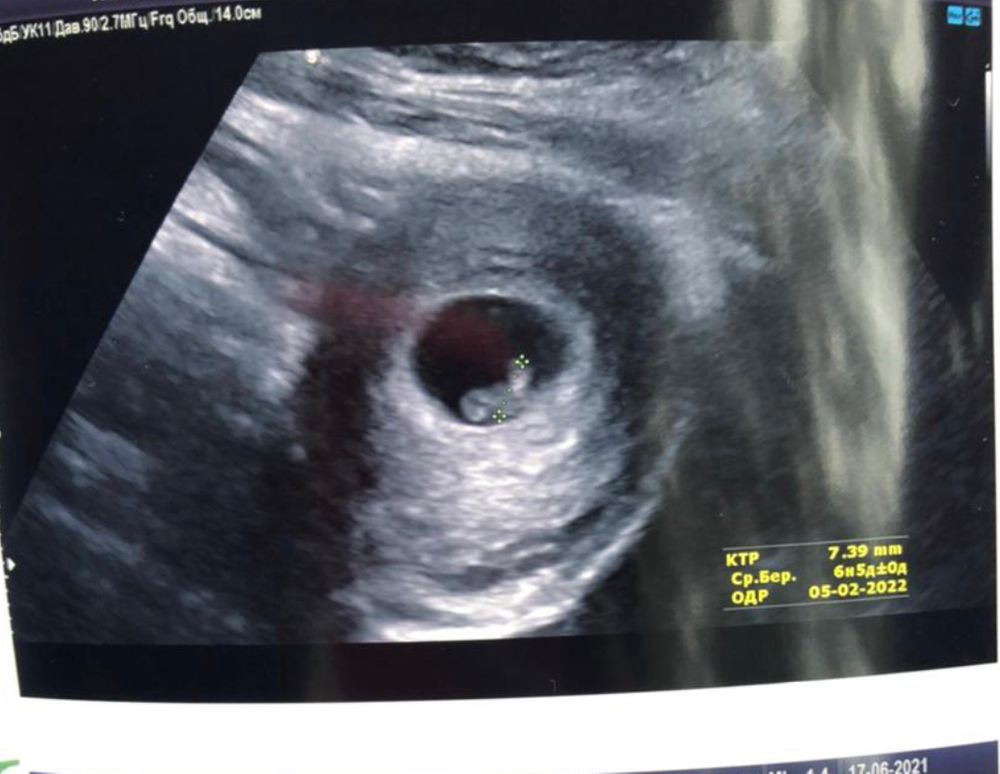

Метод Рамзи

Мальчик по этому методу

Мальчик